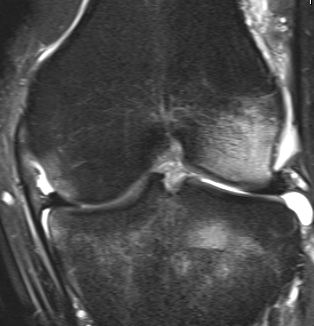

Normal ACL on MRI

Characteristics

- straight structure

- able to see continuity of fibres from tibial to femur

- parallel to intercondylar notch

- no anterior subluxation of the tibia

- normal to have some increased signal due to adipose and synovial tissue

Coronal MRI with LFC bone bruising Sagittal MRI with terminal sulcus LFC Sagittal MRI with bone bruise posterolateral tibial plateau